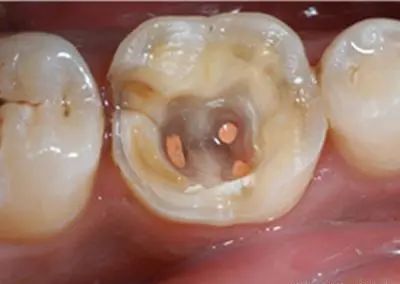

第三阶段:牙齿超过一半烂掉,说明已经重度蛀牙,细菌伤及牙髓牙神经,还伴随着剧烈疼痛,牙神经病变这时得根管治疗处理,挽救伤痕累累的牙齿。

一般医生会给你局部麻醉,清除根部坏死的牙髓,抽出牙神经后就不会那么痛,但有些牙齿根部长得歪,这时抽神经的难度较大,所以麻醉过程中效果不是很好,而插根管的数量得看牙齿具体位置,前面的牙齿一至两根,像大牙这种就得三至四根,插得越多难度就会增加。